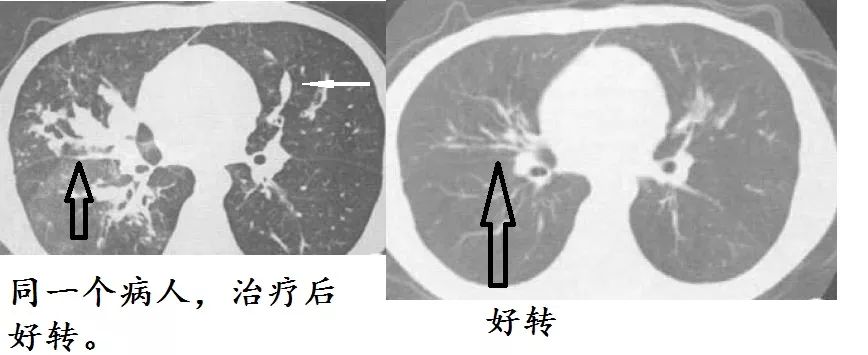

男,23岁,反复咳嗽,咳痰,喘息20年,加重2个月。从3岁开始喘息。7年前咳嗽加重,咳棕色痰栓。血嗜酸粒细胞升高,为16%。 曲霉抗原皮试呈快速阳性反应。血清总lgE为1812 Iu/ml(参考值<100 Iu/ml)。CT:支气管扩张,扩张的支气管主要分布在肺门周围,也叫中心性支气管扩张。

确诊变应性支气管肺曲霉病,给予糖皮质激素及伊曲康唑口服液治疗。6个月后复查,病灶好转,支扩好转,症状好转,全部都好转。